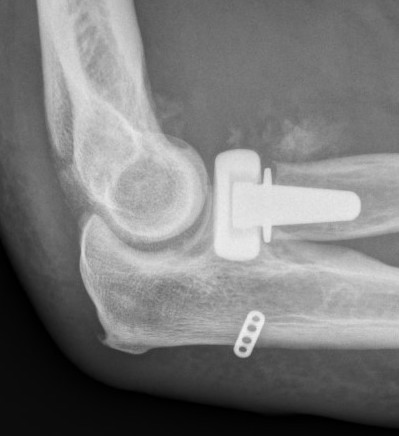

Universal posterior approach with radial head replacement and medial approach with medial buttress plate

coroncorocoronoid